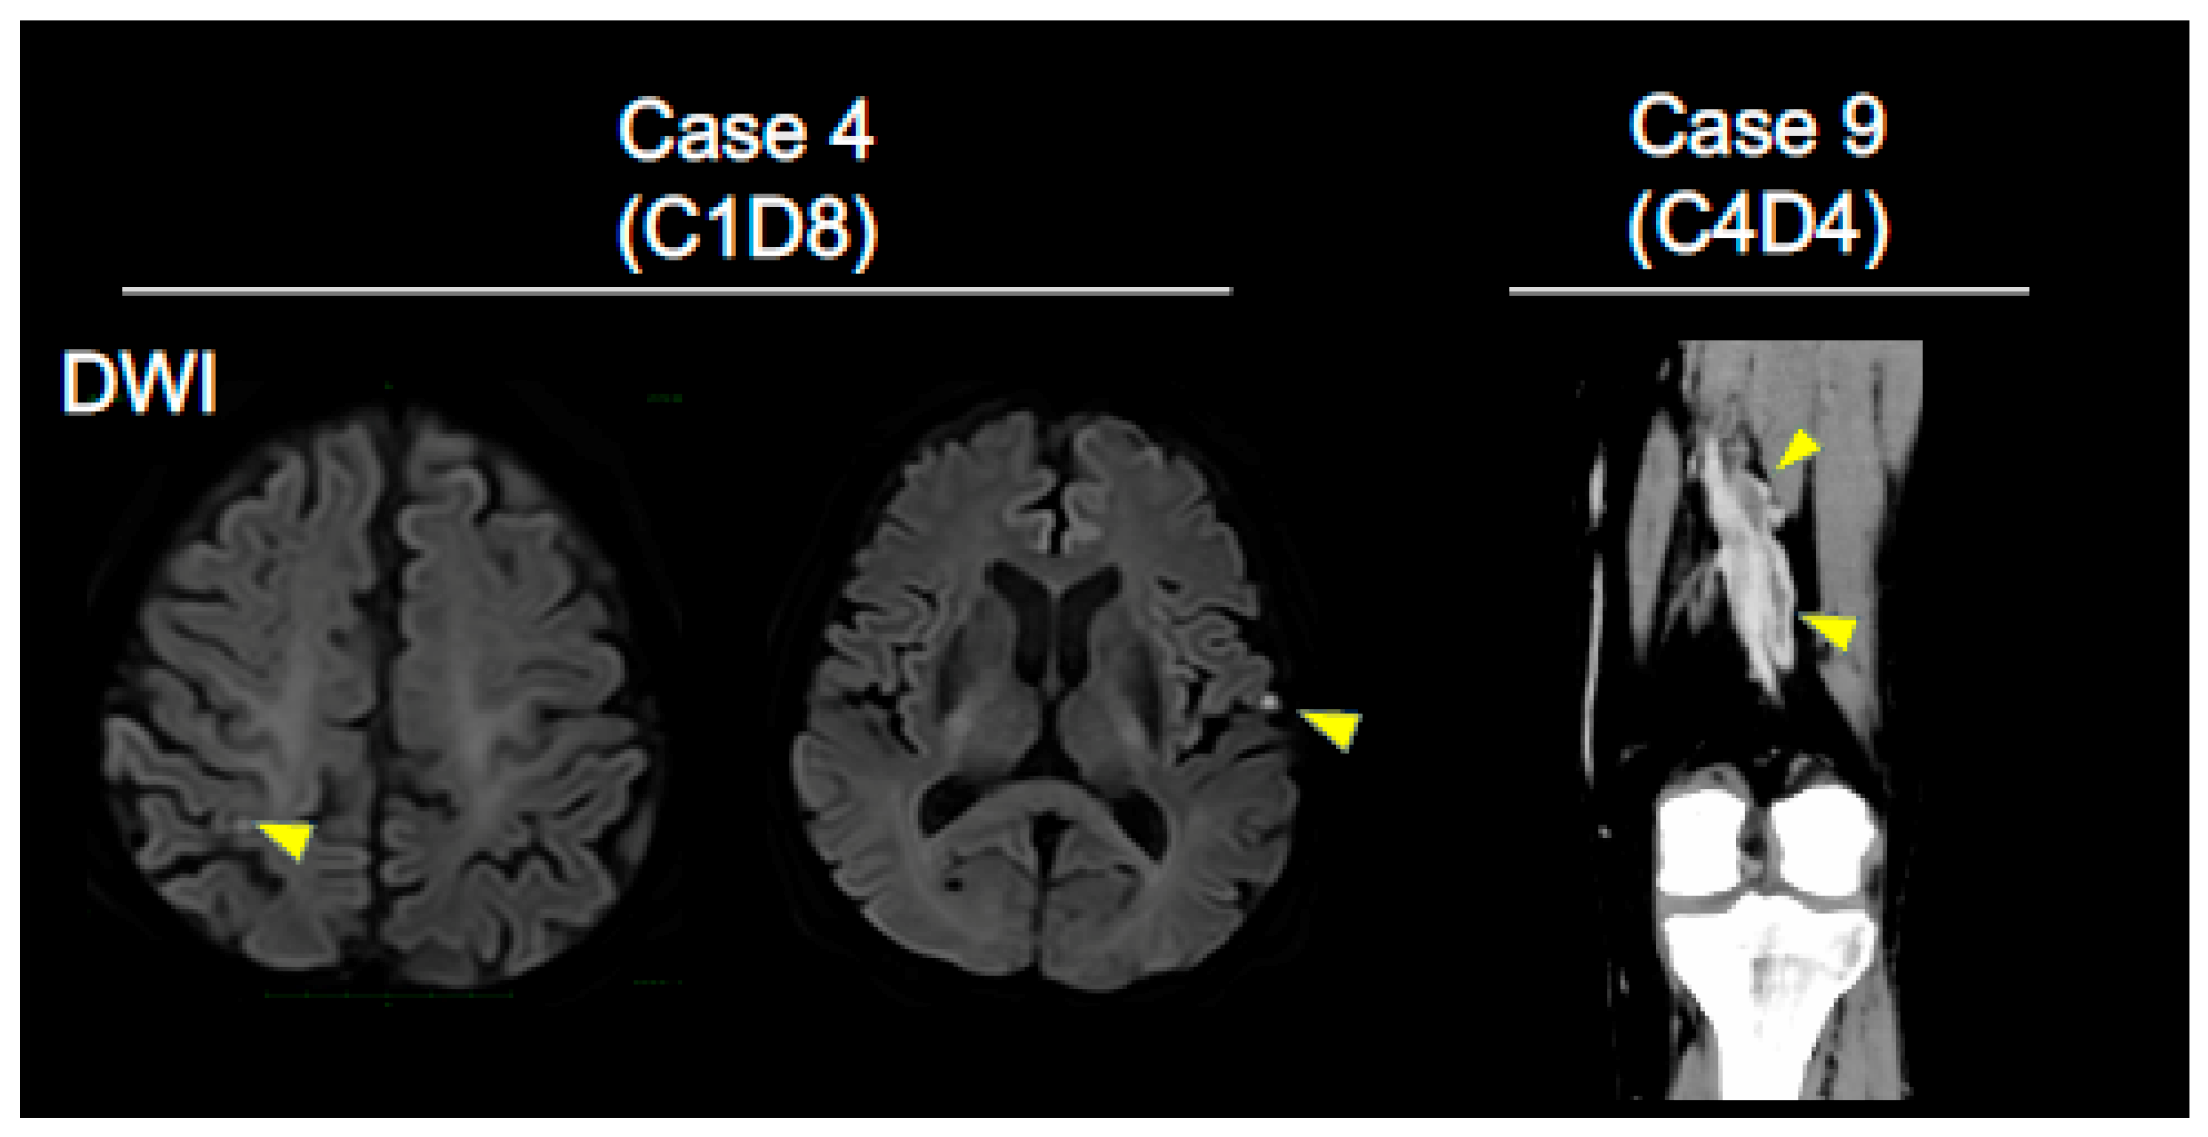

| 4 | 72/M | Multiple cerebral infarcts | 1 | Atezolizumab/3 | 1 | Sq/IIIA recurrence | ≥50% | NE | ||

| 9 | 68/F | DVT, Bronchial hemorrhage | + | 2, 2 | Nivolumab/3 | 1, 4 | Adeno/IVB | 1–24% | PR | |